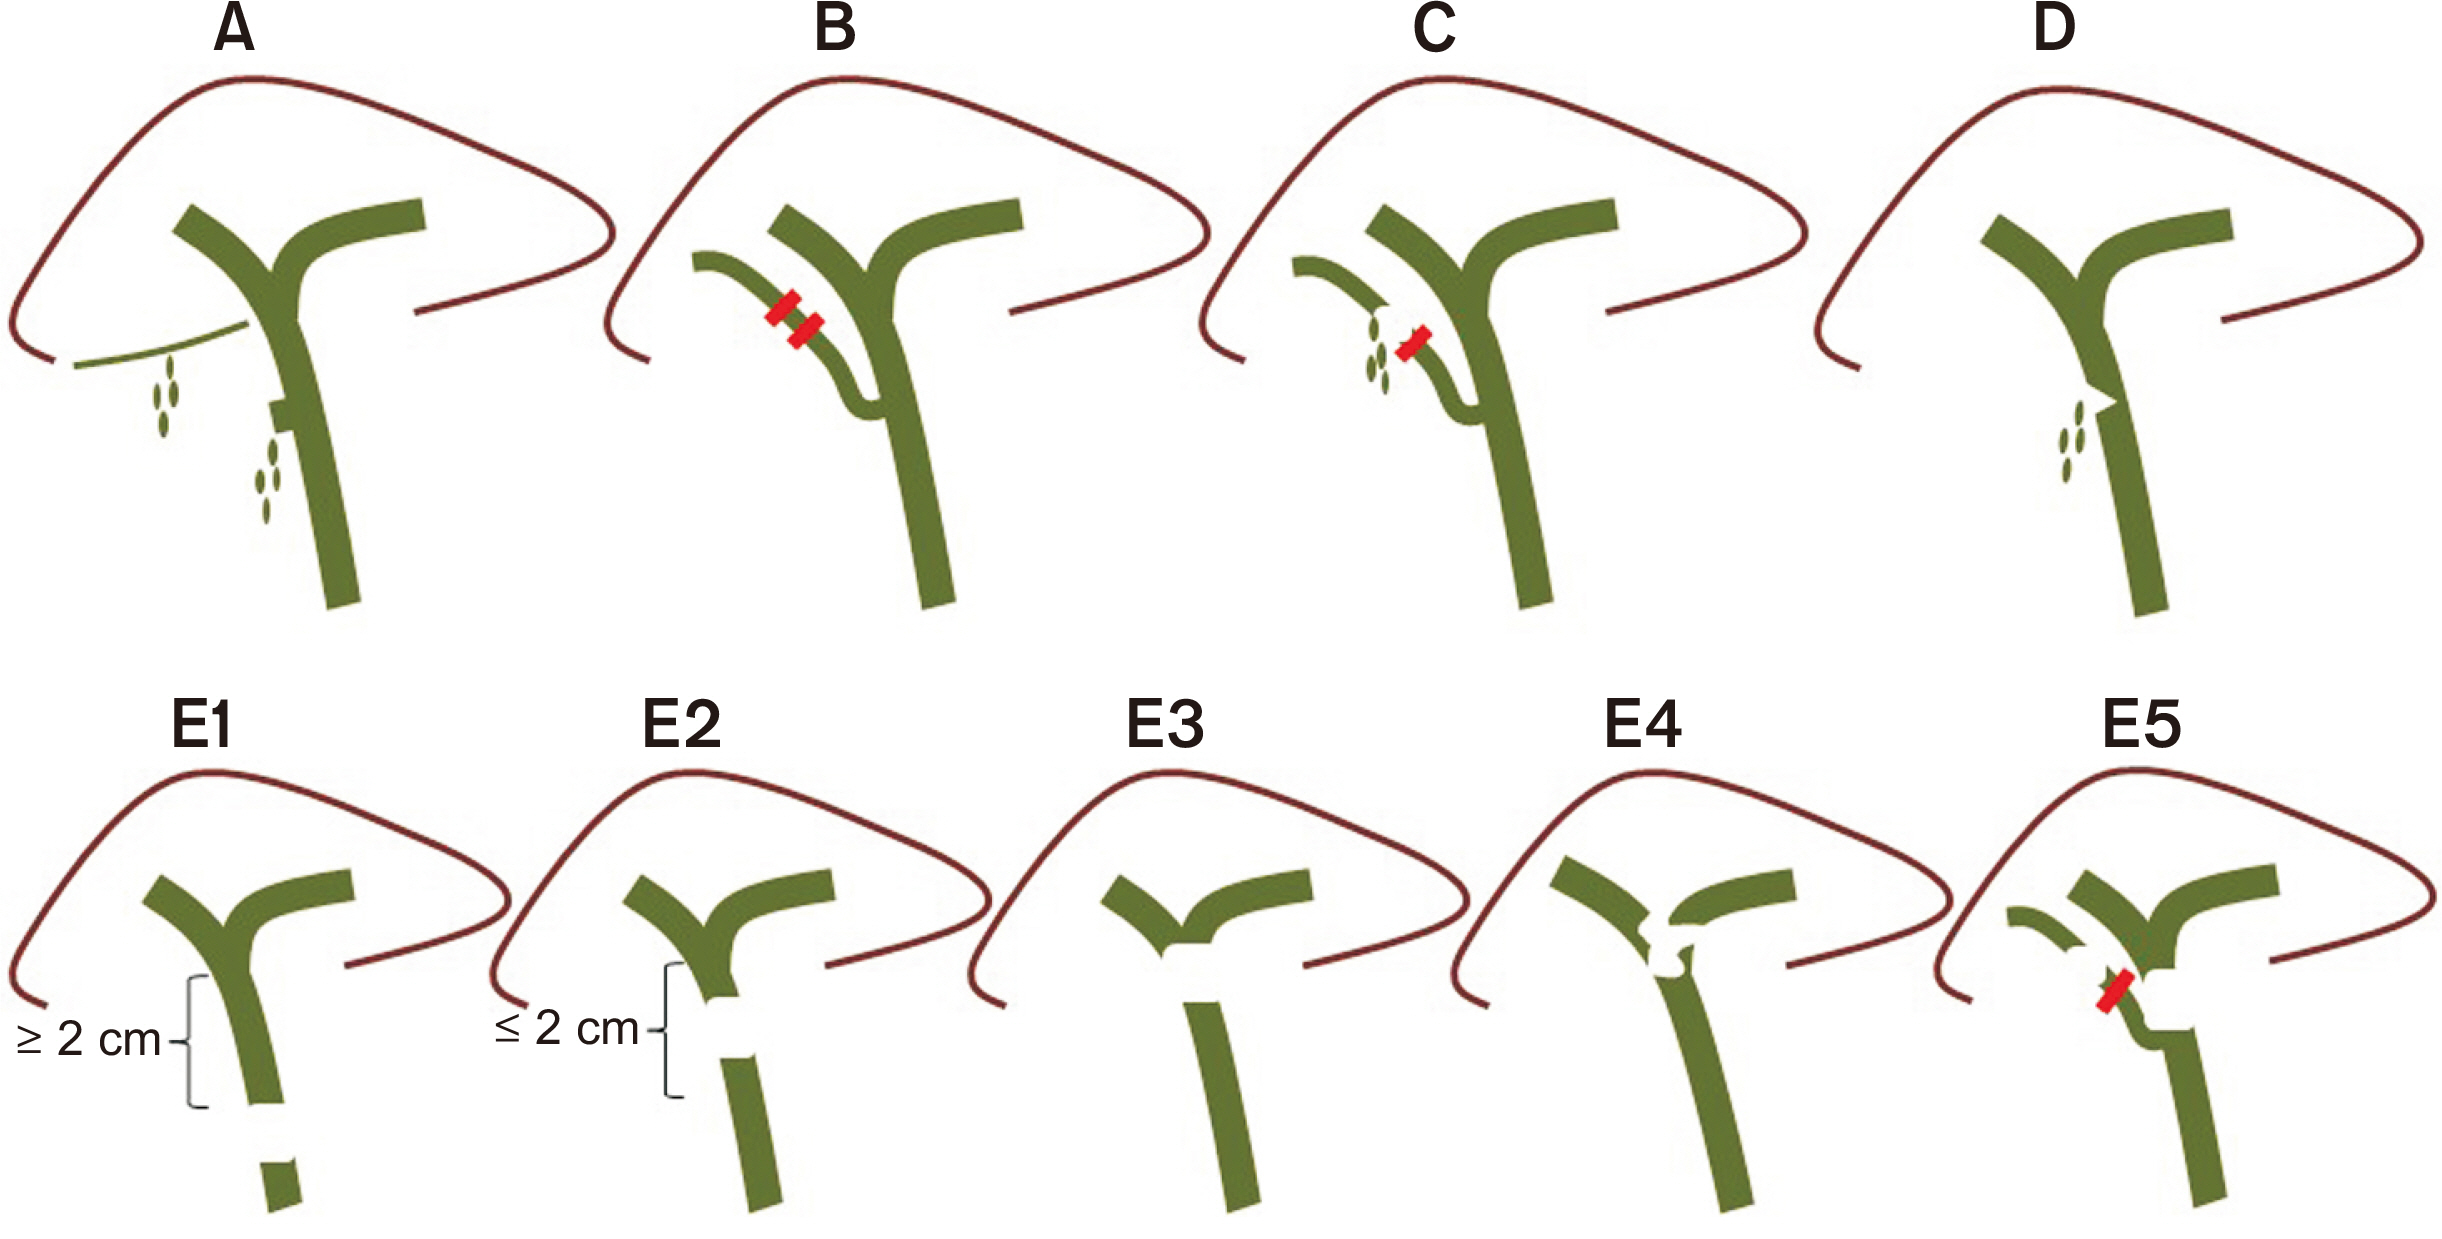

- Bile duct injuries are a serious issue, and their surgical treatment carries the risk of morbidity and mortality. In selected cases, non-surgical treatments are possible, even for total strictures. We outline the technique and results of using magnetic compression anastomosis (MCA) to treat post-cholecystectomy bile duct stricture (PCBDS), in two female patients. Initially, a bilio-cutaneous tract was established via external biliary drainage, followed by the positioning of both endoscopic and percutaneous biliary magnets. After their approximation and subsequent removal, a fully covered self-expandable metal stent (FCSEMS) was deployed across the stricture. The magnet coupling was successfully achieved within the first two weeks of placement. The FCSEMS was maintained for durations of 12 and 16 months. Follow-up durations were 28 and 15 months post-FCSEMS removal. Both patients remain asymptomatic, with normal laboratory and imaging studies, and no adverse events were reported. MCA proves to be a safe and effective method for treating selected cases of total PCBDS. However, further studies and long-term follow-up are required to fully assess the efficacy of this technique.

Article7. Jang SI, Choi J, Lee DK. 2015; Magnetic compression anastomosis for treatment of benign biliary stricture. Dig Endosc. 27:239–249. DOI: 10.1111/den.12319. PMID: 24905938.

Article15. Jang SI, Rhee K, Kim H, Kim YH, Yun J, Lee KH, et al. 2014; Recanalization of refractory benign biliary stricture using magnetic compression anastomosis. Endoscopy. 46:70–74. DOI: 10.1055/s-0033-1358907. PMID: 24254385.

Article16. Jang SI, Do MY, Lee SY, Cho JH, Joo SM, Lee KH, et al. 2024; Magnetic compression anastomosis for the treatment of complete biliary obstruction after cholecystectomy. Gastrointest Endosc. 100:1053–1060.e1054. DOI: 10.1016/j.gie.2024.05.009. PMID: 38762041.

Article17. Do MY, Jang SI, Cho JH, Joo SM, Lee DK. 2022; Magnetic compression anastomosis for treatment of biliary stricture after cholecystectomy. VideoGIE. 7:253–255. DOI: 10.1016/j.vgie.2022.03.005. PMID: 35815159. PMCID: PMC9264143.

Article18. Ödemiş B, Başpınar B, Tola M, Torun S. 2022; Magnetic compression anastomosis is a good treatment option for patients with completely obstructed benign biliary strictures: a case series study. Dig Dis Sci. 67:4906–4918. DOI: 10.1007/s10620-022-07381-3. PMID: 35050430.